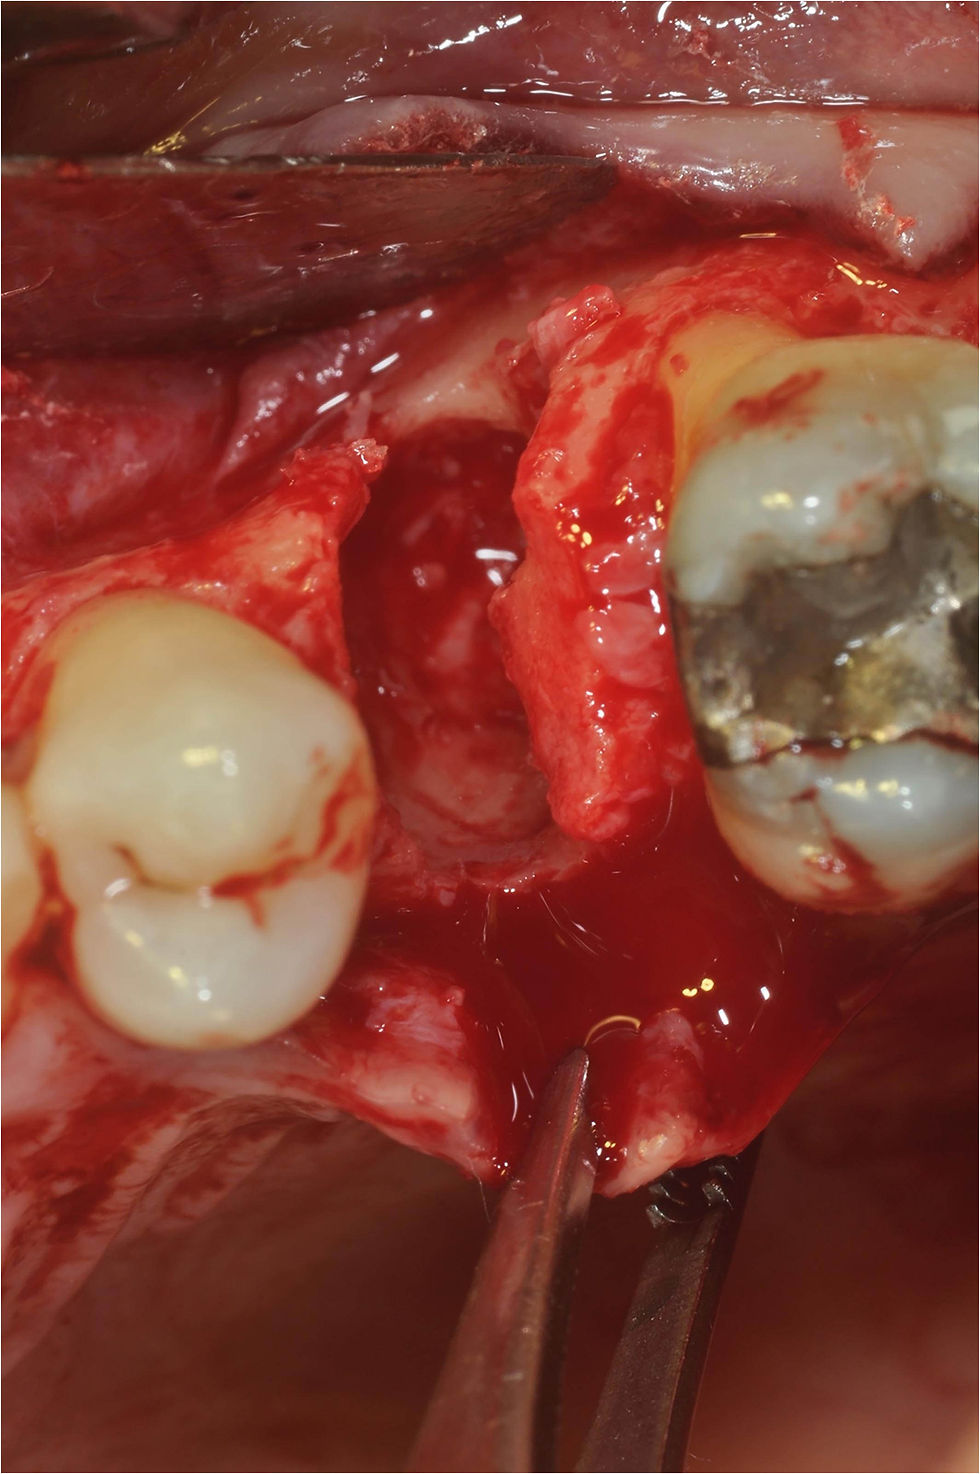

Extracted element.

Exposure of the lesion for its three-dimensional evaluation.